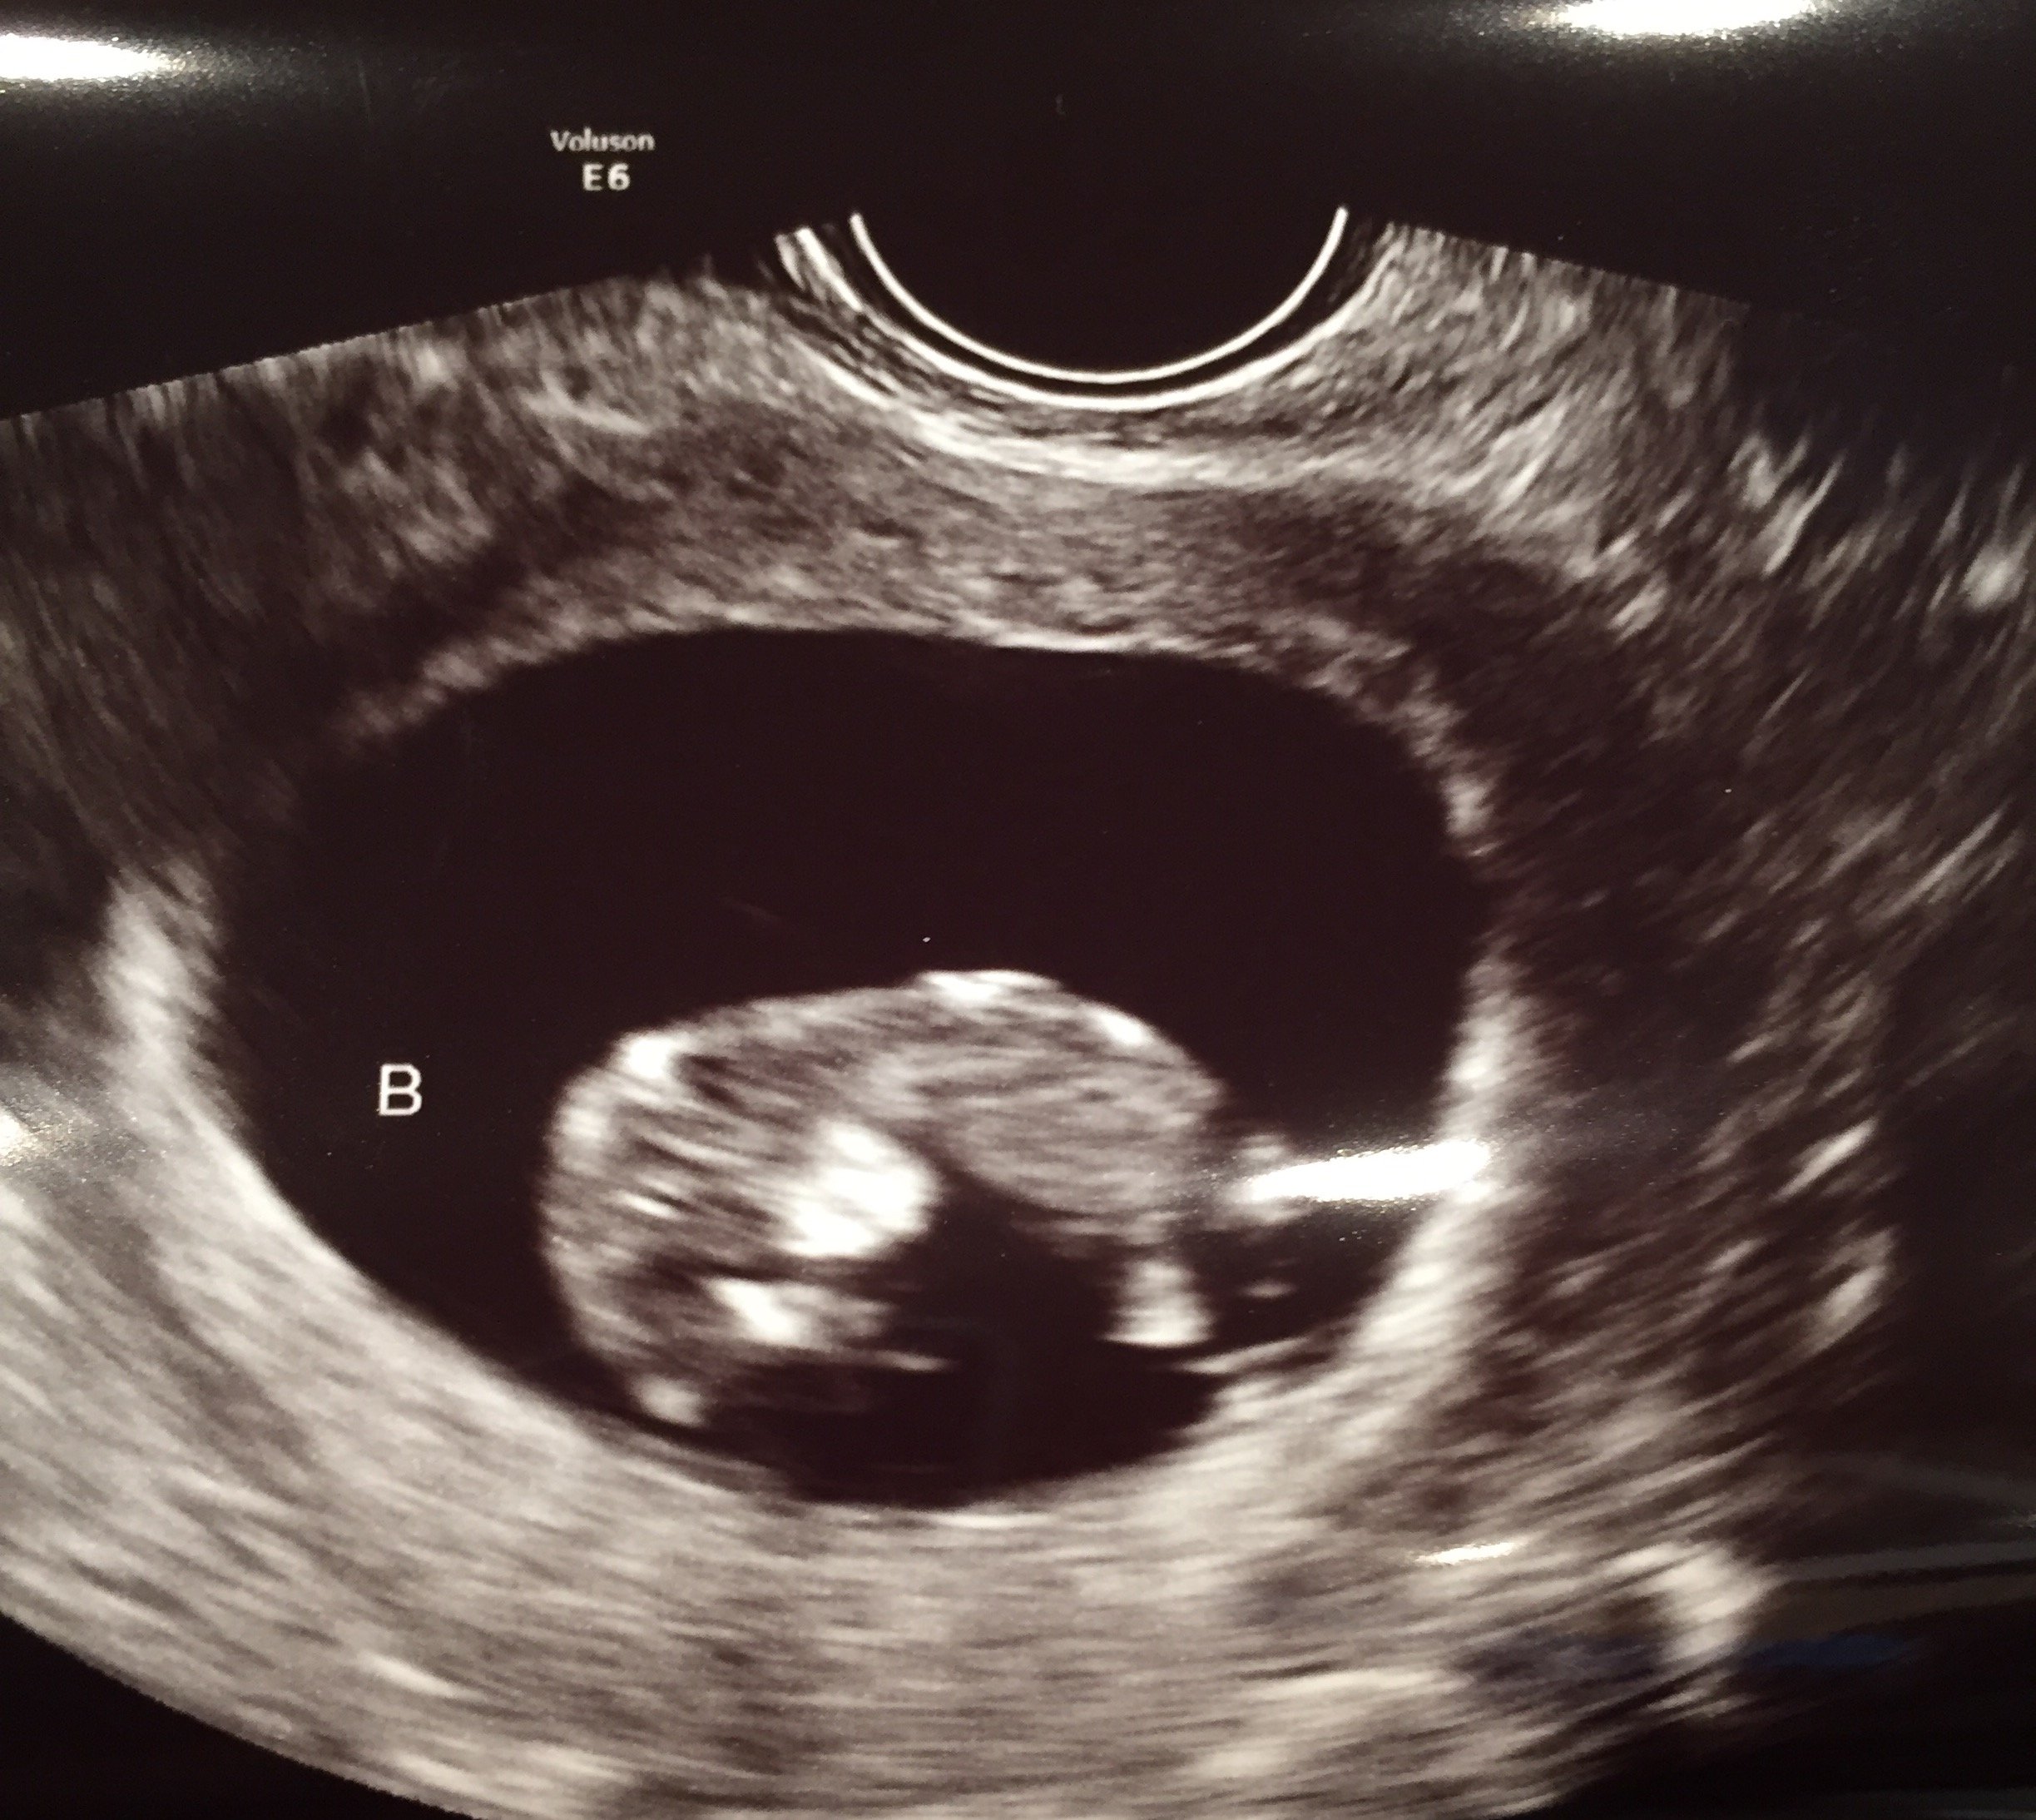

Had my NT scan today. Such a huge difference from my 7 week ultrasound. It actually had arms and legs this time!!

12w 1d